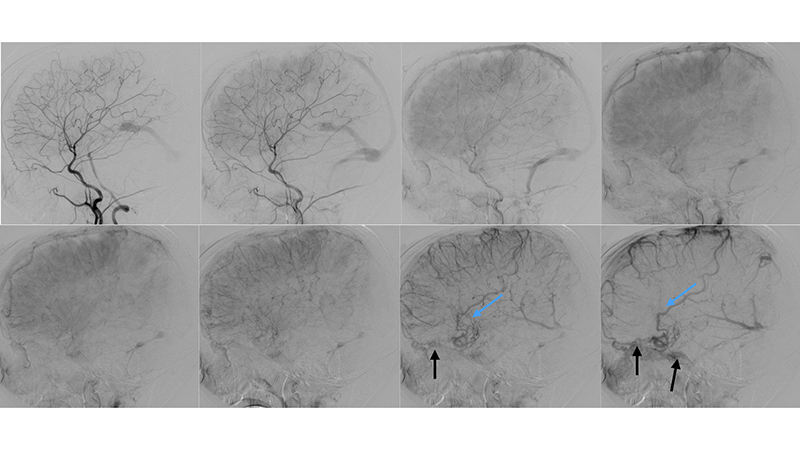

- Πλαγία λήψη κατά την έγχυση στην δεξιά έσω καρωτίδα. Υπάρχει εξεσημασμένη φλεβική συμφόρηση του άνω οβελιαίου κόλπου, προς το σύστημα της φλέβας του Troland (μπλέ βέλος), τον σηραγγώδη κόλπο και τό έδαφος του προσθίου κρανιακού βόθρου (μαύρα βέλη) και το πτερυγοειδές πλέγμα.

- Πλαγία λήψη κατά την έγχυση στην αριστερή έσω καρωτίδα. Η φλεβική παροχέτευση της αρτηριοφλεβώδους επικοινωνίας προς το σύστημα του άνω οβελιαίου κόλπου (κόκκινα βέλη) με εξεσημασμένη φλεβική συμφόρηση και κινητοποίηση παράπλευρων διαμυελικών φλεβών προς το σύστημα της επιπολής μέσης εγκεφαλικής φλεβός (μπλέ βέλος) και διά του σφηνοβρεγματικού κόλπου προς τον σηραγγώδη κόλπο ενώ το εν τω βάθει φλεβικό δίκτυο αποχετεύεται μέσω των αναστομώσεων με το σύστημα της εν τω βάθει μέσης εγκεφαλικής φλεβός (διακεκομμένο μπλέ βέλος) προς το σύστημα επίσης του σηραγγώδους κόλπου.